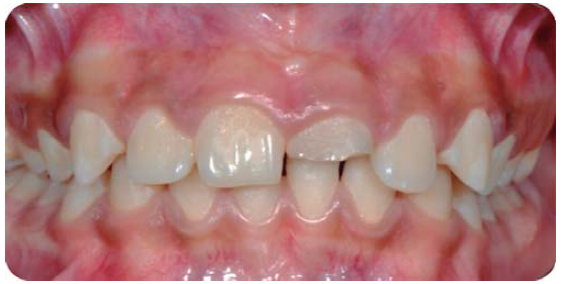

Paciente masculino de nueve años de edad, que presenta LDT en el incisivo central superior izquierdo, por golpe al caer de una patineta; durante la urgencia le realizaron el tratamiento del sistema de conductos del diente 21.

En la exploración clínica extra e intraoral sólo se observa la fractura dental (Figura 26), en la radiografía se observa el tratamiento de sistema de conductos (Figura 27).

Fractura complicada de corona del diente 21, radiográficamente se observa un diente despulpado con tratamiento de sistema de conductos y sin lesión periapical; periodontalmente presenta gingivitis inducida por placa dentobacteriana (Figura 28).